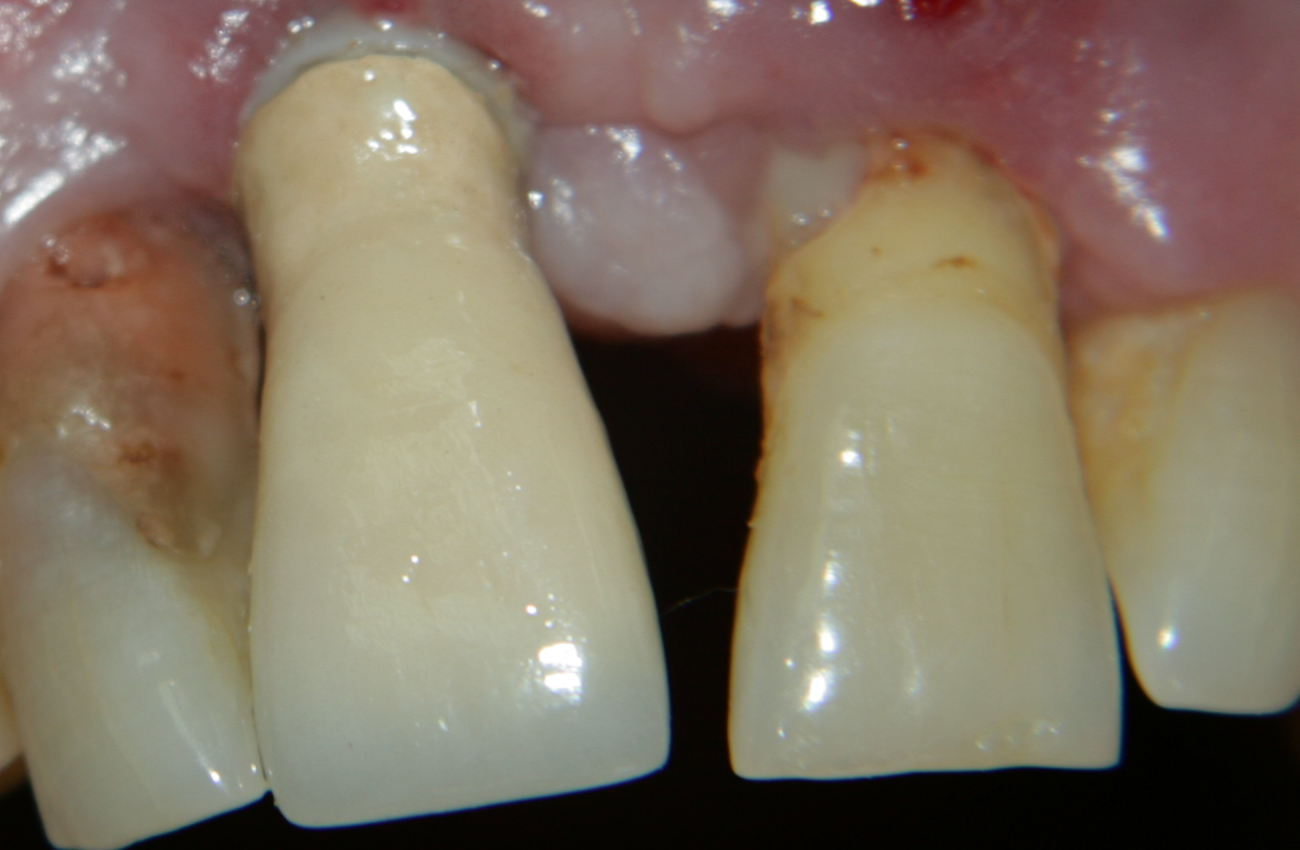

Зъб с тежък пародонтален възпалителен процес - горният централен

резец вляво. Зъбът е леко прорастнал, с тъмночервена гингива, с дълбок

пародонтален джоб, от който изтича гноевиден ексудат. Зъбът вдясно е стар

имплантат - система TBR - който е поставен пет

години преди да се развие пародонтитът на левия централен резец. Към момента

въпреки недобрата устна хигиена на пациента (вижда се зъбна плака около

имплантатната шийка) старият имплант е стабилен и не създава никакви

оплаквания на пациента. Според схващанията на клиницистите отпреди 8 - 10

години само имплантолог -

камикадзе би се наел да постави имплантат имедиатно при такава клинична

ситуация. Все пак, както всяка друга научна дисциплина, и

имплантологията търпи развитие. Днес всички клиницисти и изследователи

При масиране на венеца около зъб 21 се вижда капка гноен ексудат.

Зъбът е с изразена подвижност, трета степен, силно болезнен при перкусия и

дори при докосване с език. Наличието на тежък пародонтит ни принуди да

назначим антибиотичен прием на Клиндамицин по схема 3 х 600 милиграма два

дни предоперативно, като приемът на

антибиотика продължи още шест дни постоперативно до пълната епителизация

на раната - общата продължителност на антибиотичния курс достигна осем дни.

За повече информация относно

антибиотиците

в имплантологията кликнете

тук...

Всичко протече без усложнения от възпалителен характер.